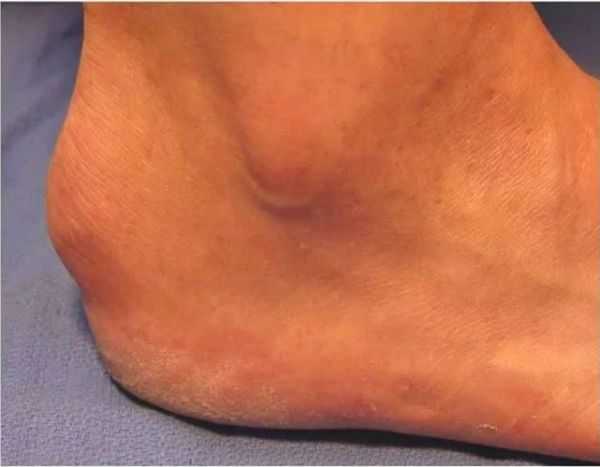

Обычно заболевание развивается в пубертатном возрасте, хотя возможно и более раннее начало – описаны случаи болезни Шинца у пациентов 7-8 лет. Начинается исподволь. Возможны как острые, так и постепенно усиливающиеся боли в пятке. Болевой синдром возникает преимущественно после нагрузки (бега, продолжительной ходьбы, прыжков). В области пяточного бугра появляется видимая припухлость, однако признаки воспаления (гиперемия, характерное давление, жжение или распирание) отсутствуют. Отличительными признаками болевого синдрома при болезни Шинца является появление болей при вертикальном положении тела через несколько минут или сразу после опоры на пятку, а также отсутствие болей в ночное время и в покое.

Тяжесть заболевания может различаться. У части пациентов болевой синдром остается умеренным, опора на ногу нарушается незначительно. У другой части боли прогрессируют и становятся настолько невыносимыми, что опора на пятку полностью исключается. Больные вынуждены ходить, опираясь только на средний и передний отделы стопы, у них возникает потребность в использовании трости или костылей. При внешнем осмотре у большинства пациентов выявляется умеренный локальный отек и атрофия кожи. Нередко имеет место нерезко или умеренно выраженная атрофия мышц голени. Характерной особенностью болезни Шинца является кожная гиперестезия и повышенная тактильная чувствительность пораженной области. Пальпация области пяточного бугра болезненна. Разгибание и сгибание стопы затруднены из-за боли.

Припухлость выше пятки появляется при запущенной форме заболевания, но при этом не сопровождается температурой и покраснением. Процесс развития болезни Шинца у детей проходит по-разному: иногда в течение месяца, а в редких случаях может продолжаться на протяжении двух лет.

По-научному болезнь называется «остеохондропатия апофиза кости пяточной». Данное заболевание было выявлено и описано в самом начале прошлого века шведским хирургом с интересной фамилией Хаглунд, позднее ее изучил и сам Шинц, в честь которого и назвали недуг. Болезнь Шинца у детей совсем еще маленьких (до десяти лет) встречается очень редко, потому что все их косточки и хрящи мягки и податливы. Начинается с возникновения острой, а также постепенно усиливающейся боли в районе пяточного бугра, особенно после определенной нагрузки, например, длительной ходьбы. Над бугром пяточной кости появляется припухлость без видимых признаков острого воспаления – жжения и появления красноты. Если стопу разогнуть или начать пальпировать, то в этой области пятки сразу же даст о себе знать выраженная боль. Чаще всего болезненный процесс приходится на какую-то одну сторону пятки.